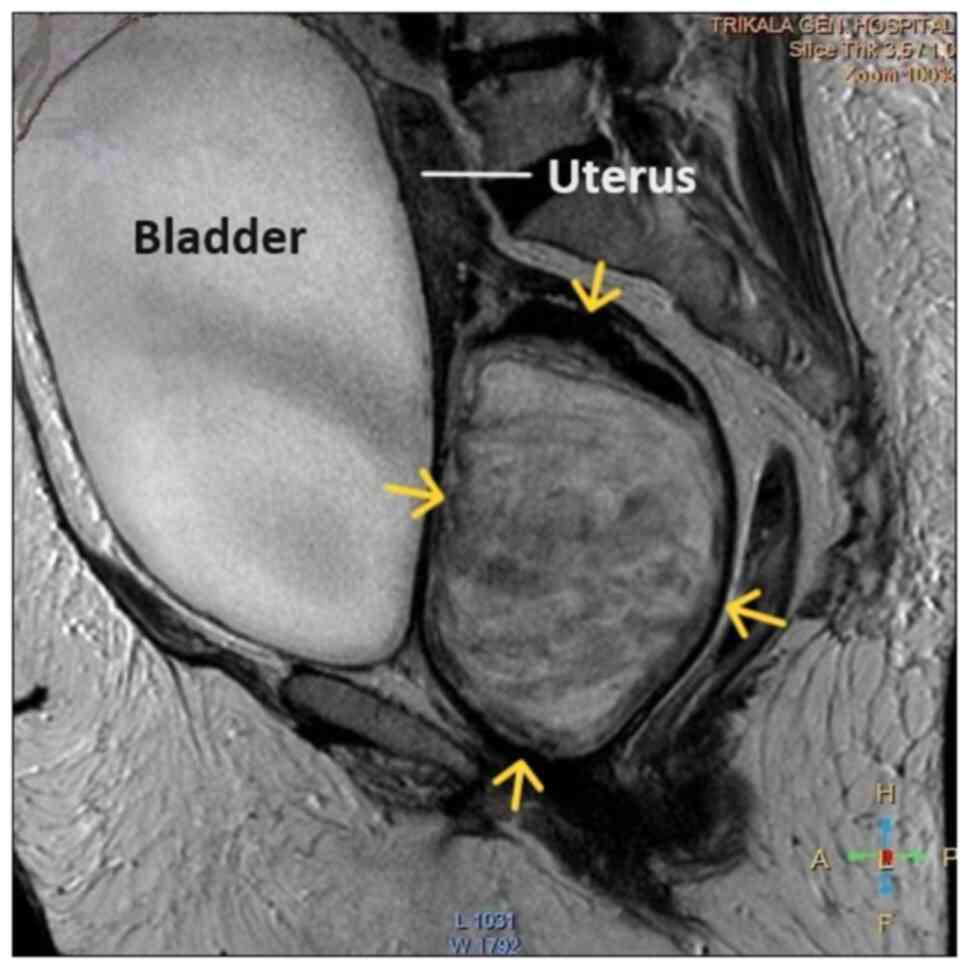

Figure 5

Magnetic resonance imaging of a large prolapse pedunculated submucosal uterine leiomyoma: The depicted urinary bladder distention with internal non-homogeneity of the cervical canal and presence of a lobulated lesion in the endocervix (yellow arrows) was misdiagnosed as an intracervical leiomyoma.

Upon a gynecological examination and upon the inspection of the vagina with a speculum, the cervix was not visible. In the upper third of the vagina, in the anatomical position of the cervix, a large solid mass was observed; the position of the external cervical os could not be clearly identified by visual inspection or palpation (Fig. 1). The transvaginal ultrasonographic findings were inconclusive. The scan detected the presence of a large well-circumscribed mass, with a maximum diameter of 10 cm, at the anatomical position of the cervix, raising suspicion of an intracervical leiomyoma (Fig. 2). A renal ultrasound revealed the bilateral dilatation of the pelvicalyceal system and the ipsilateral proximal ureter (Fig. 3). Furthermore, a computed tomography scan was performed, which revealed significant bladder dilatation and internal non-homogeneity of the cervical canal throughout its entire length, measuring 105x95x90 mm. This lesion caused the thinning of the external wall of the cervix and anterior displacement of the bladder. At the same time, it exerted compression on the posterior wall of the bladder, and malignancy arising from the cervix could not be excluded (Fig. 4). Additionally, computed tomography confirmed the dilatation of the pelvicalyceal system bilaterally up to the ureterovesical junction, accompanied by localized renal cortical thinning and lobulated contour of the left kidney. Magnetic resonance imaging was performed to further elucidate the findings of computed tomography. Magnetic resonance imaging revealed marked bladder distention with internal non-homogeneity of the cervical canal and the presence of a lobulated lesion that protruded intracanal with dimensions of 100x85x105 mm (Fig. 5). This finding was attributed to a large intracervical leiomyoma, strongly ruling out the possibility of cervical malignancy. The levels of tumor markers, namely carcinoembryonic antigen, cancer antigen 125, cancer antigen 15-3 and cancer antigen 19-9 were within the normal range.